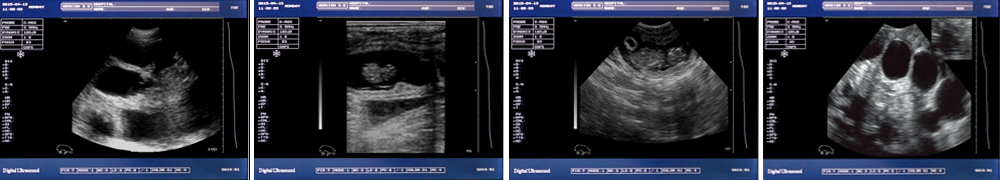

● 顯示模式:B、B/B、B+M、M、4B;

一流的數(shù)字成像技術(shù) 圖像更清晰